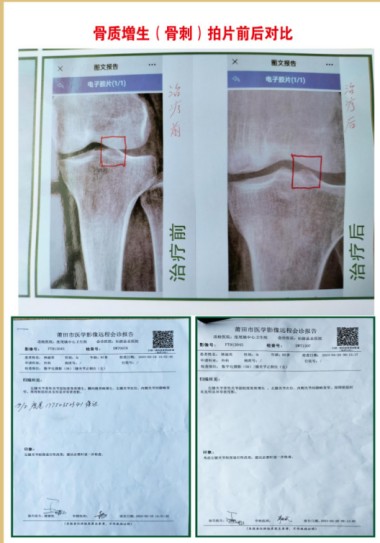

①病历依据,2012年一2016年,53岁,女,腰椎左侧弯L4,LS1。椎间隙狭窄,L3,L4,L5,LS1椎间盘向周围膨出,双侧椎间孔稍狭窄,L4,L5椎间盘积气并向周围膨出,L3,L4,L5,LS1不同程度骨质增生,走路身体变形,怕动手术风险,五年时间治疗无效,外用药水热敷配合手法操作自己治疗,22天治愈。

②病历依据,2003年一2018年依据,52岁,女,腰椎,L4,L5向椎管内突出1公分,隐窝变窄,L3,L4,5,LS1硬膜囊受压,骨质增生,走路身体三节弯歪斜,外用药水热敷,配合手法操作自己治疗,20天治愈。

③病历依据,66岁,男,生理曲度变直,椎体边缘毛糙,变尖,L3,L4,L5椎间盘膨出,L5,Ls1椎间盘向内突出,L4,L5,突出3.4㎜,椎间盘L3,L4内真空,椎间隙变窄L5,LS1,走路弯曲,外用药水热敷,配合手法操作治疗服中药15天,一个月治愈。

④病历依据,65岁,女,腰椎突出畸形L4,L5向前移位,L5椎体双侧椎弓峡部欠连续,L5,LS1椎间内真空,L5,LS1椎间隙变窄,L3,L4,L5椎间盘向后突出,相应硬膜囊受压,左侧神经根受压,椎体边缘骨质增生,外用药水热敷,配合手法操作自己治疗1个月治愈。

⑤病历依据,67岁,男,L4节向前移位,生理曲度变直,部分椎体骨质增生L4,L5,椎间盘向后偏左突出3.1㎜,硬膜囊受压,L5,LS1椎间盘向后膨出,硬膜囊受压,部分椎体积影,外用药水热敷,配合手法操作自己治疗,服中药15天治愈。